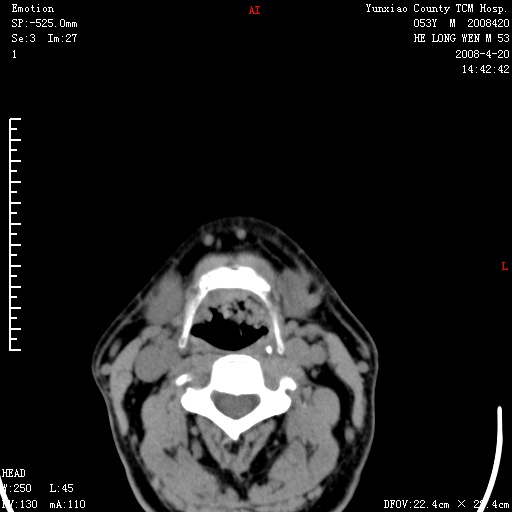

双侧扁桃体肿大:考虑化脓性扁桃体炎。

双侧扁桃体肿大 ,考虑扁桃体炎。

双侧扁桃体肿大,建议结合临床!

双侧扁桃体肿大 ,考虑扁桃体炎

应该有症状,体检此部位不是常规体检项目,支持双侧扁桃体肿大 ,考虑扁桃体炎,但还是强化一下吧。

双侧扁桃体肿大,考虑扁桃体炎,应做一下增强

显示部分为舌扁桃体,腭扁桃体未见显示。会厌显示欠规则,建议喉镜。